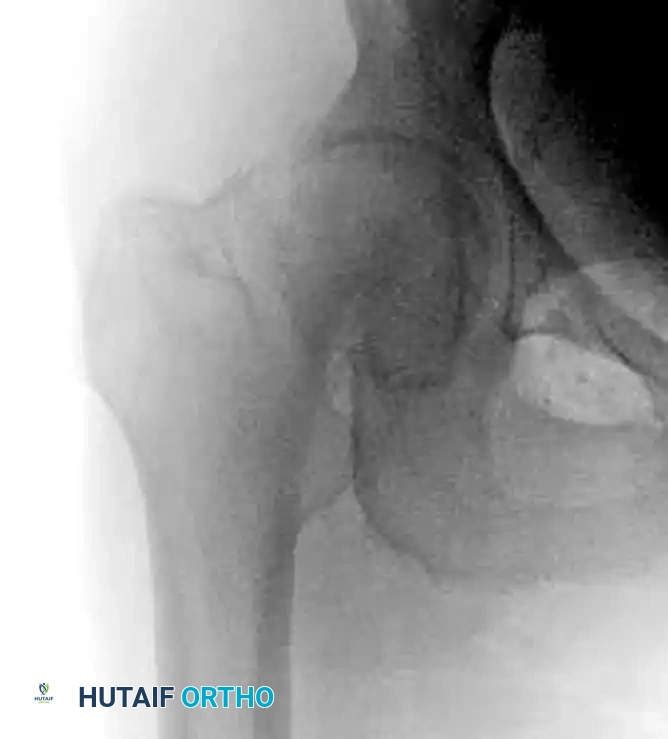

The Tip-Apex Distance (TAD)

Proper placement of the lag screw is the single most important surgeon-controlled variable in reducing the incidence of implant failure, specifically lag screw "cut-out" through the superior femoral head.

The Tip-Apex Distance (TAD), described by Baumgaertner, is calculated by summing the distance from the tip of the lag screw to the apex of the femoral head on both the AP and lateral radiographs, corrected for magnification.

* Rule of Thumb: As the TAD increases above 25 mm, the risk of biomechanical failure and cut-out increases exponentially. A center-center position inherently minimizes the TAD.

Integrity of the Lateral Wall

The lateral trochanteric wall acts as a critical buttress for the proximal fragment. When treating intertrochanteric fractures with a CHS, the integrity of this wall must be rigorously evaluated.

Clinical Pearl: In a landmark series, 22% of patients with a fractured lateral wall (A3 fractures or iatrogenic fractures in A1/A2) treated with a CHS required a reoperation within 6 months. Strikingly, 74% of these lateral wall fractures occurred intraoperatively during reaming or plate impaction.

Studies by Im and Chung identified iatrogenic lateral wall comminution as the most significant predictor of excessive fracture displacement. If iatrogenic comminution occurs, the surgeon must strongly consider augmenting the construct with a trochanteric stabilizing plate (TSP) or abandoning the CHS in favor of an intramedullary nail. Therefore, the CHS should be used with extreme caution in fractures more complex than A2.1.